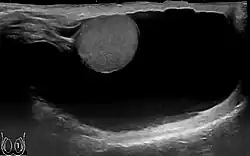

Diagnostic methodExamination, ultrasound[3]

The swelling is soft and non-tender, large in size on examination, and the testis cannot usually be felt. The presence of fluid is demonstrated by transillumination. These hydroceles can reach a huge size, containing large amount of fluid, as these are painless and are often ignored. They are otherwise asymptomatic, other than size and weight, causing inconvenience. However the long continued presence of large hydroceles causes atrophy of testis due to compression or by obstructing blood supply. In most cases, the hydrocele, when diagnosed early during complete physical examination, are small and the testis can easily be palpated within a lax hydrocele. However Ultrasound imaging is necessary to visualize the testis if the hydrocele sac is dense to reveal the primary abnormality. But these can become large in cases when left unattended. Hydroceles are usually painless, as are testicular tumors.

The accuracy of the diagnosis must be ascertained. Great care must be taken to differentiate a hydrocele from a scrotal hernia or tumor of the testicle. Ultrasound imaging can be very useful in these cases. A hernia usually can be reduced, transmits a cough impulse, and is not translucent. A hydrocele cannot be reduced into the inguinal canal and gives no impulse on coughing unless a hernia is also present. In young children a hydrocele is often associated with a complete congenital type of hernial sac.

A common method of diagnosing is by attempting to shine a strong light (transillumination) through the enlarged scrotum. A hydrocele will usually pass light, while a tumor will not (except in the case of a malignancy with reactive hydrocele).